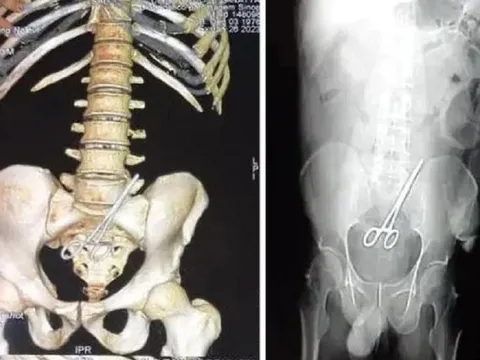

Bác sĩ bỏ quên kéo trong bụng bệnh nhân khiến người này "đứng ngồi không yên"

Một bác sĩ phẫu thuật người Brazil đã bỏ quên chiếc kéo trong cơ thể một chính trị gia địa phương khi phẫu thuật, khiến người này ốm liên miên.